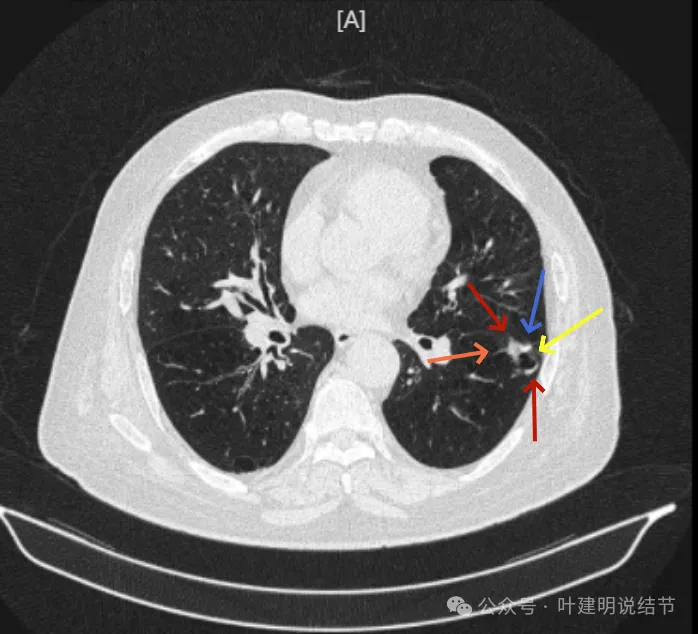

明显壁厚薄不均的囊腔灶,囊壁基本实性,表面不平,内壁不光滑,且邻近叶间裂并牵拉叶裂。

表面毛糙不平,部分区域有点像锯齿状。

表面不平细毛刺,中间空腔欠光滑、囊壁厚薄不均。

上图囊壁较厚,密度较高,轮廓与边界较清。

病灶边上也有多发小空泡样征,说明病灶有收缩力或对周围结构有影响。

上图显得像混合密度伴偏心空腔征。

上图是病灶边缘部位有血管走向病灶侧,并达病灶的地方有异常增粗。